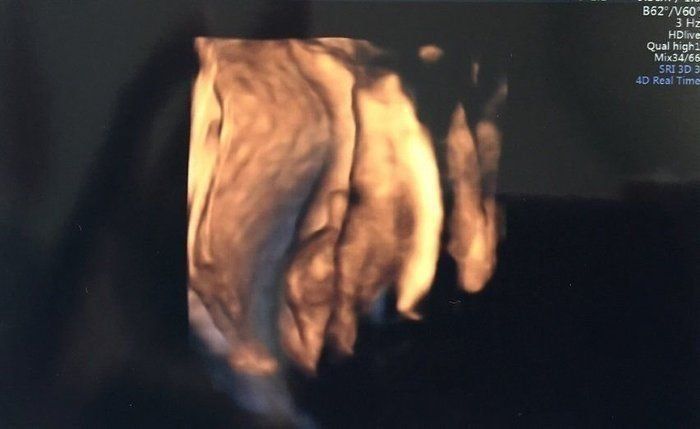

マダムまかろんさんの妊娠28週目のエコー写真 3D画像を撮影することを決意

健診を受けていた病院からもらうエコー画像は、ごく一般的な2Dタイプ。私は、この時期だけの赤ちゃんの姿を記念に残したかったことと、赤ちゃんが本当に元気に育っているのかをはっきりと確認したかったので、3D画像の撮影だけでも予約可能な産院を探すことを決意。この時すでに赤ちゃんがこれ以上大きくなると映りにくくなるというぎりぎりのタイミングでした。